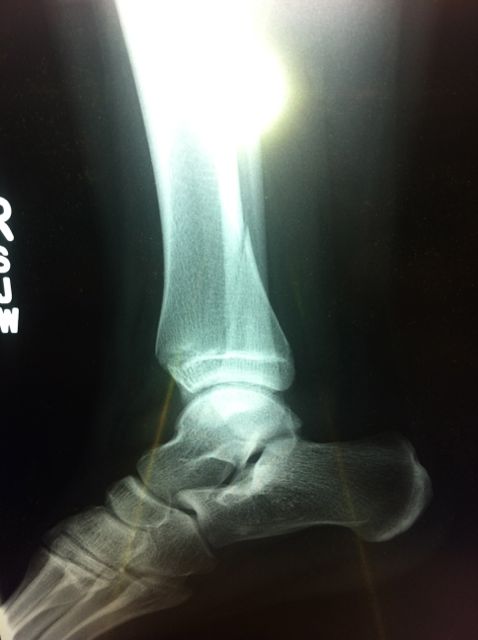

Följande dag, på söndagen tog Maken henne till Akuten eftersom vi gissade att detta antingen handlade om en ordentlig stukning eller ett benbrott. Jodå, svar fick vi:

Så, nu har vi då en Dotter på kryckor, fast om allt går bra kommer gipset bort om två veckor när nya röntgenplåtar tas och sedan läggs ett nytt gips på i ytterligare två veckor.